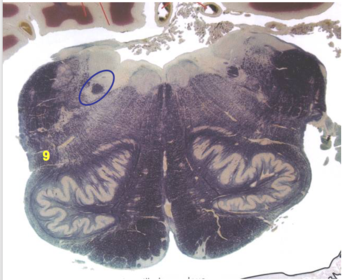

| Superior vestibular nucleus | |

| Medial lemniscus | |

| Trapezoid body | |

| Ventral trigeminothalamic tract | |

| Superior olive | |

| Longitudinal pontine fibers (corticospinal tract) | |

| Transverse pontine fibers (dark fibers) | |

| Pontine nuclei (pale) | |

| Central tegmental tract | |

| ALS | |

| Medial longitudinal fasciculus | |

| Middle cerebellar peduncle | |

| Superior cerebellar peduncle | |

| Anterior spinocerebellar tract | |

| Principle nucleus of V | |

| Mesencephalic V tract | |

| Trigeminal root fibers | |

| Motor nucleus of V | |

| Cerebellar vermis | |

| Lateral lemniscus | |

| Longitudinal pontine fibers (c-spinal, c-bulbar, c-pontine fibers) | |

| Transverse pontine fibers (dark) | |